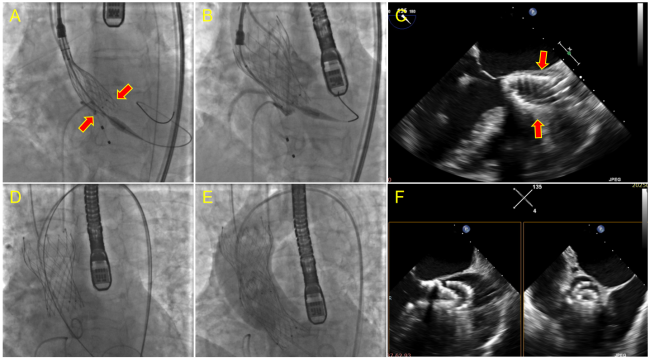

During the deployment, subvalvular stent compression was observed (Figure A). After the valve was deployed (Figure B), transesophageal echocardiogram (TEE) showed an olive-shaped deformation (Figure C). Immediately after the catheter delivery system was withdrawn, the valve migrated into the ascending aorta (Figure D). Subsequently, we decided to adopt a valve-in-valve (ViV) strategy, and the second valve (a Venus A23) was progressively deployed to achieve a tandem configuration with the first valve (Figure E and F). Both the left and right coronary artery ostia remained unobstructed, and only mild aortic regurgitation was noted.

To the best of our knowledge, we are the first to report an “olive sign” under TEE during TAVI, characterized by an olive-shaped deformation of the valve stent immediately after prosthetic valve deployment. This sign indicates subvalvular stent compression, resulting in valve instability and potential migration into the ascending aorta. The underlying mechanism may involve unevenly distributed calcification, causing the valve stent to establish focal rather than circumferential contact with the annulus.